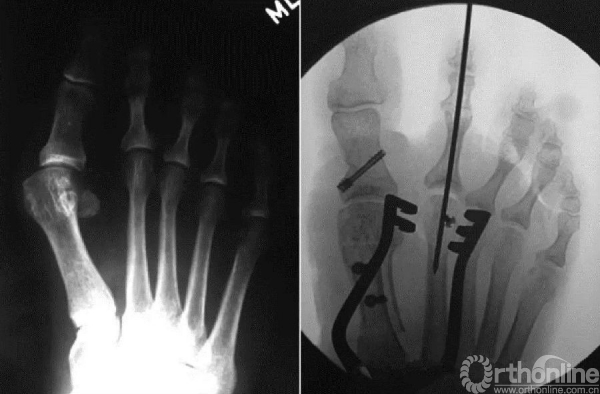

跖板损伤后跖趾关节不稳造成锤状趾/交叉趾

在行跖侧切口之前,先自跖骨头背侧中心向跖侧贯穿打入一枚克氏针,以帮助定位关节负重区

对于伴有骨/关节病变需要行骨性手术者,先从背侧入路完成所有骨性手术,再跖侧入路修复跖板